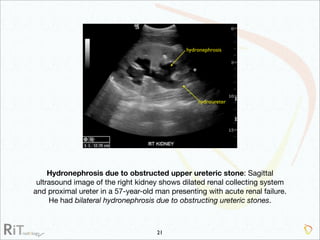

The document discusses the imaging modalities used in evaluating acute abdominal pain, including radiography, ultrasound, computed tomography (CT), and scintigraphy, highlighting their roles, indications, and limitations. It emphasizes the complexity of diagnosing acute abdomen due to its broad differential diagnoses and the necessity for accurate imaging to inform timely management. Additionally, the document outlines considerations such as patient history, contrast medium reactions, and appropriate imaging criteria based on various clinical presentations.